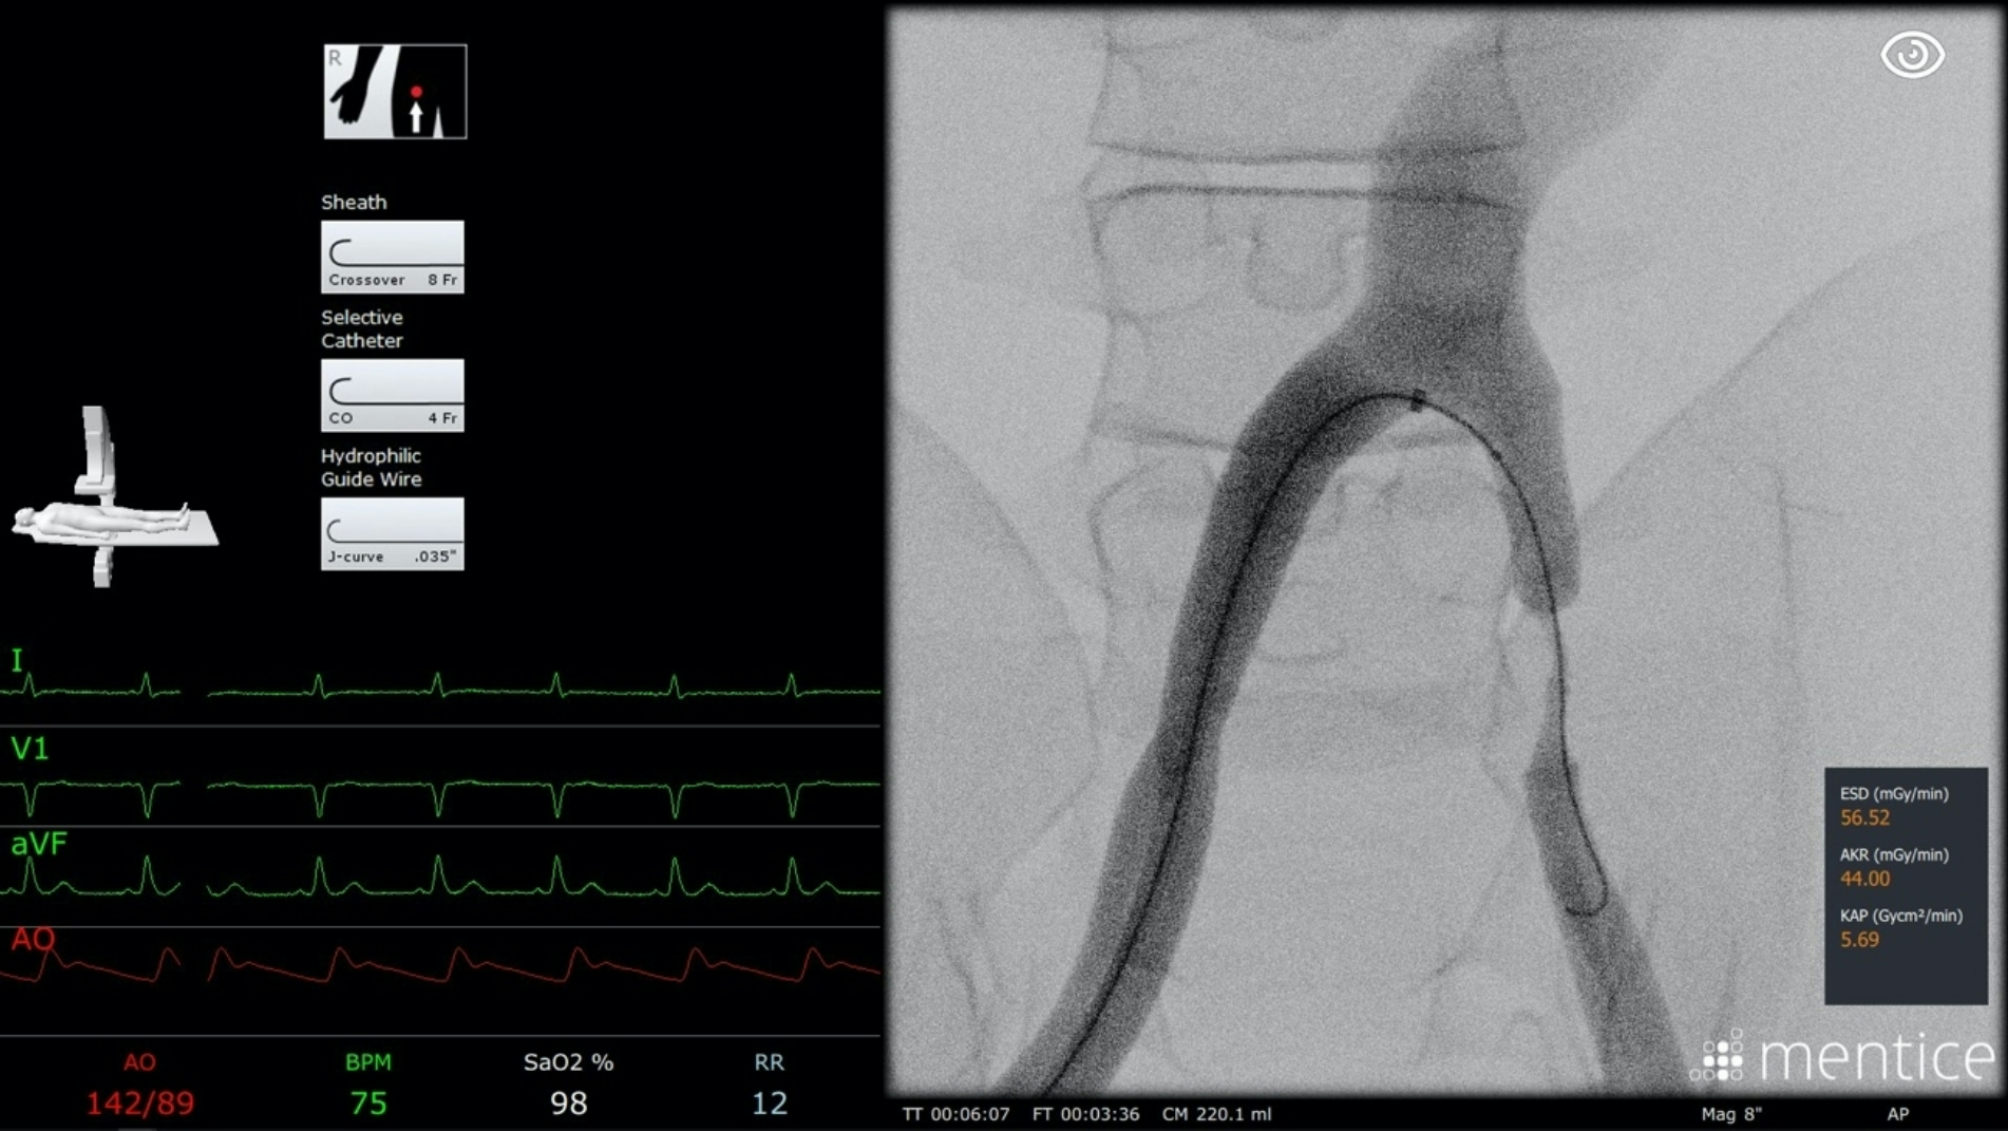

Fig. 4

From: Simulator training for enhanced interventional radiology education

Screenshot of the simulator user interface during the treatment of a common iliac artery stenosis. The image shows the detailed interface with selected devices in the top left corner, highlighting the realistic and interactive elements of the simulation that aid in the training of angiographic procedures. The detailed and interactive interface helps participants familiarize themselves with actual procedural elements, leading to better preparation for real-world clinical scenarios.